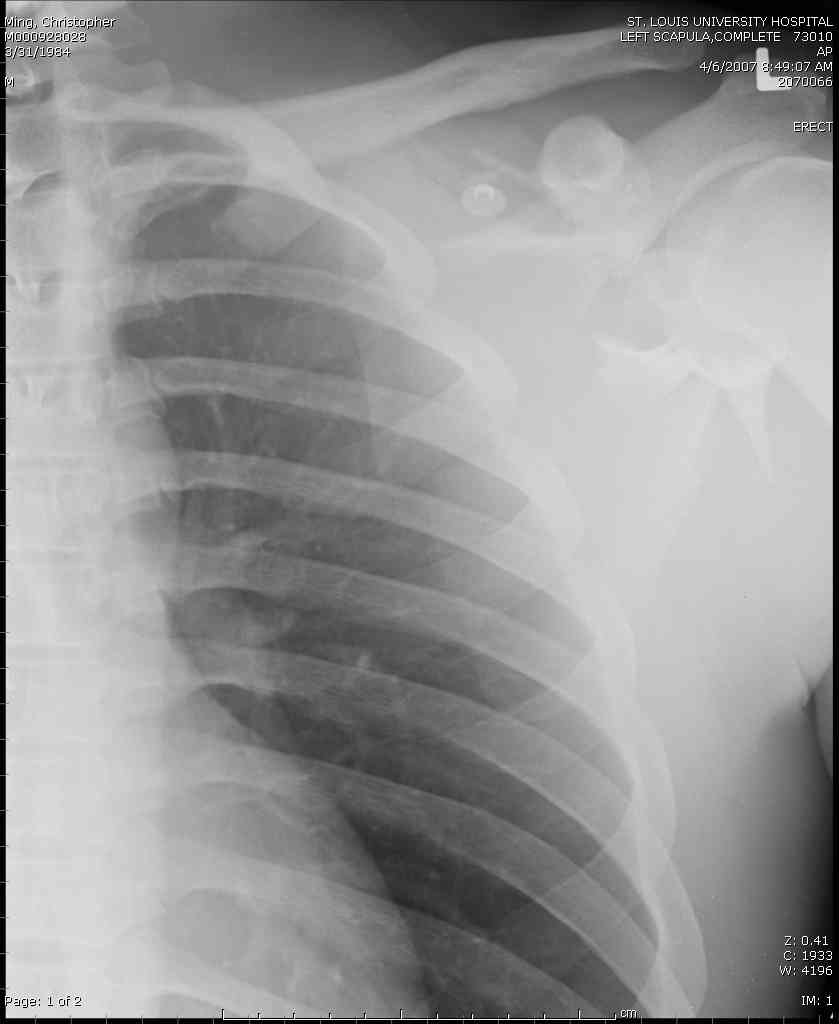

Никита, поздравляю с хорошей репозицией перелома

ключицы.

Для решения насчет оперативного вмещательства на лопатке сперва надо определиться с обьязательными ренгенологическими исследованиями, не менее трех стандартных проекций: прямая, аксиллярная и в позиции виде “Y”.

Прямую снимают под углом в 35 градусов от центра и вид “Y” в 90 градусов к нему. Несмотря на неудобства, больному необходимо сделать

аксиллярный снимок.